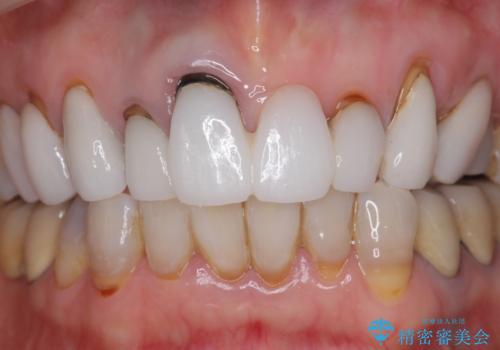

[ セラミック治療 ] 歯ぐきの際の黒ずみを改善したい

- 歯ぐきとセラミックの間の黒ずみが目立つので、きれいに治してほしい。と希望され来院されました。

歯ぐきの位置が変化しクラウン下の歯が見えるようになってしまったことで、審美障害が生じている状態です。

クラウンマージンの再設定を行うことで、黒ずんだ部分を再度覆い、審美障害を改善します。

- 52.8万円(ジルコニアクラウン×4・仮歯×4)費用は治療当時の料金となります